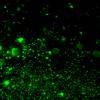

Neuronal Ceroid Lipofuscinosis (NCL) (5)